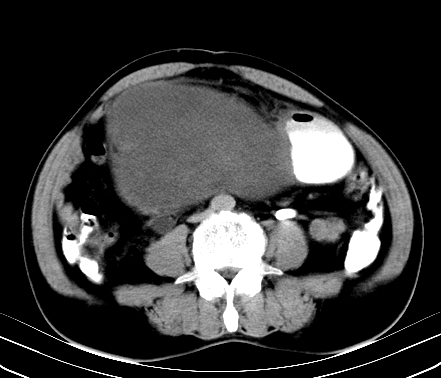

标题: CT19729B:男,74岁,因腿疼就诊,查体触腹部肿物, [打印本页]

标题: CT19729B:男,74岁,因腿疼就诊,查体触腹部肿物,

增强扫描

静脉期

延时期

【ct表现】

1、肿块巨大,往往位于腹膜后,长大后才引起症状而就诊;那么位于腹膜后的肿瘤80%为恶性肿瘤。

2、实性肿瘤,增强扫描轻度不均强化,实性肿瘤一般不是好东西。

3、肿瘤边缘似见少许脂肪样密度。

4、腹膜后未见肿大淋巴结,但肿瘤于临近的肠管及组织接触紧密。

【诊断】

腹部占位,考虑位于腹膜后的恶性肿瘤,脂肪肉瘤(实体型)可能性大。

术后病理结果:腹膜后脂肪肉瘤。